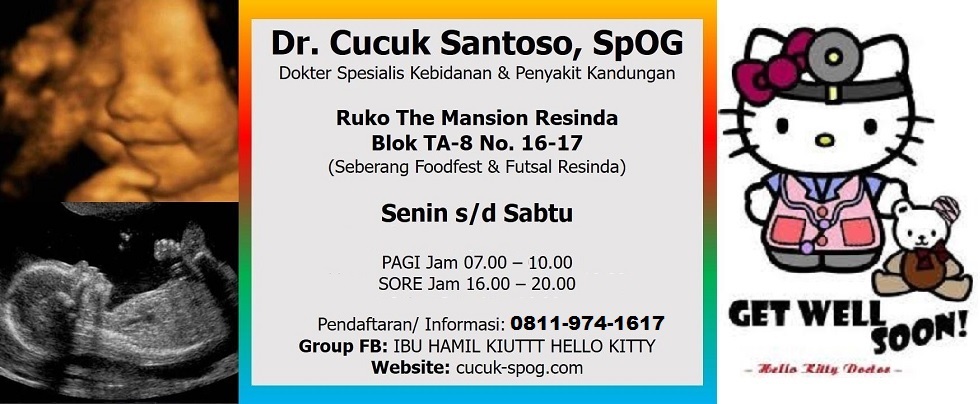

Dokter cucuk kiuttt hello kitty selalu bilang saat praktek “gak usah makan nasi banyak, tapi protein ibu ditambahin… banyakin tempe, banyakin tahu, banyakin ikan, banyakin daging, banyakin sayur… gak usah makan krupuk, gak usah makan chiki, gak usah makan mie bungkusan, jangan ngemil gorengan warung… ibu baiknya ngemilnya ikan sepat, ikan teri, ikan mujaer kecil, dendeng…”. Mohon maaf kalo dokter cucuk kiuttt hello kitty sering cerewetin ibu-ibu hamil yang males makan. semua demi kebaikan ibu hamil kiuttt hello kitty juga.

mohon maaf banget ya kalo dokter cucuk kiuttt hello kitty selalu ngomelin ibu hamil kiuttters untuk masalah makanan selama kehamilan karena dokter cucuk kiuttt hello kitty punya ambisi mencerdaskan dan menyehatkan bayi-bayi Indonesia sehingga tidak kalah bersaing dengan bayi-bayi amerika dan bayi-bayi israhell.

INFORMASI PENTING DOKTER CUCUK KIUTTT HELLO KITTY

3. Kata kunci: dokter kandungan karawang – dokter kandungan cikampek – dokter cucuk santoso – dokter kiuttt hello kitty – rumah sakit izza – rumah sakit puri asih – dr. cucuk santoso, spog – 7 zat gizi – makanan sehat selama hamil – BPJS – dokter spesialis obgyn karawang – dokter spesialis obgyn cikampek – rumah sakit di karawang – rumah sakit di cikampek – fanpage dr. cucuk santoso, spog – grup ibu hamil – group ibu hamil – kiuttt hello kitty – hello kitty